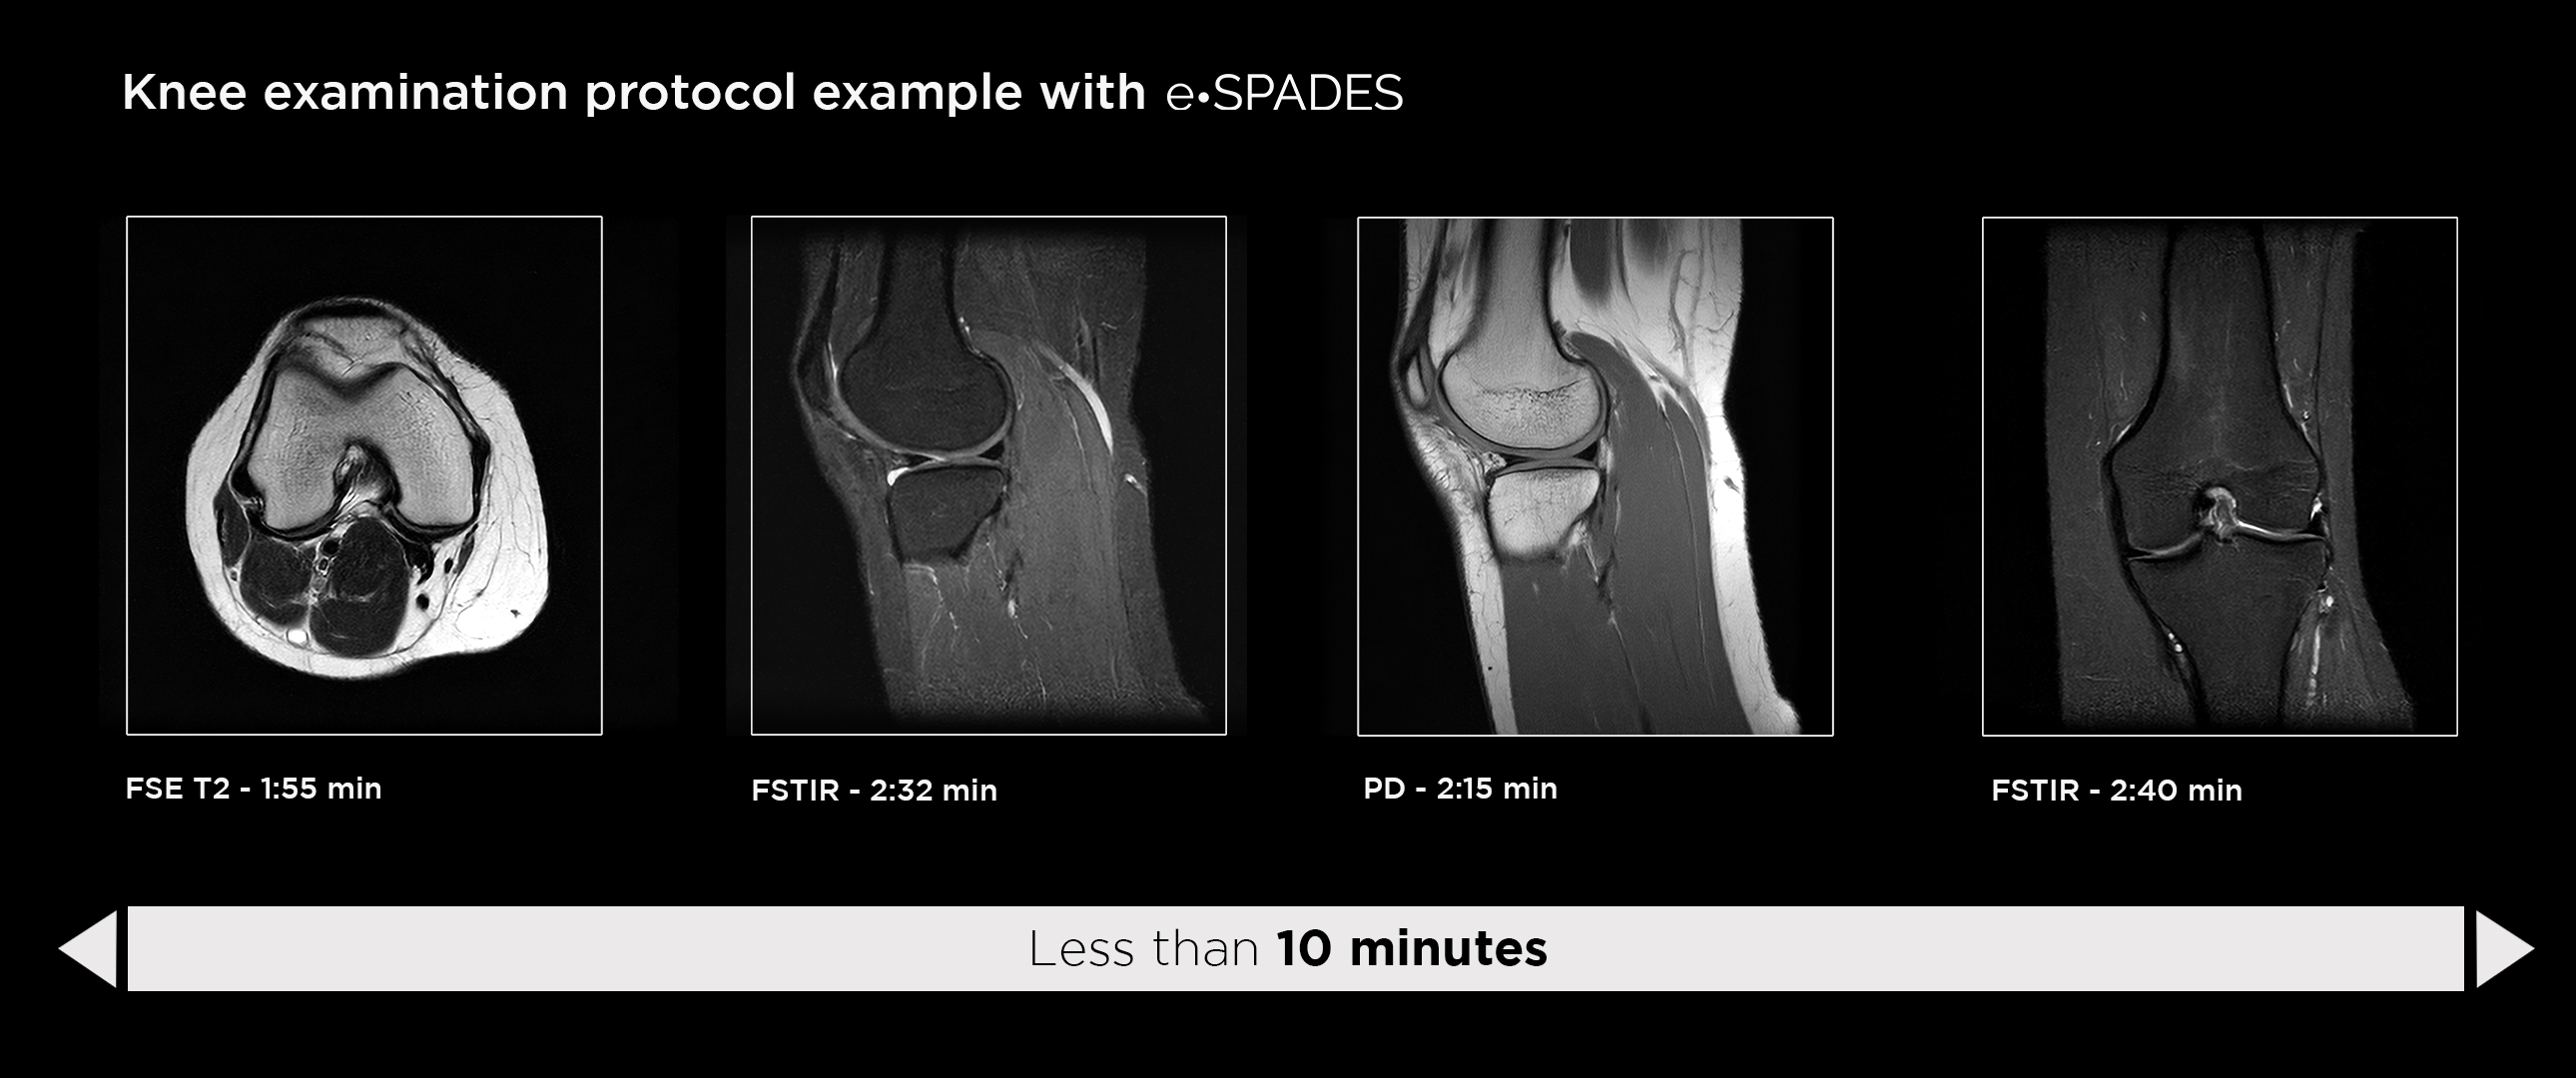

Esaote introduces Artificial Intelligence into its MRI systems as a fully integrated and customized solution. The new technological platform, e‑SPADES, consisting of advanced HW and sophisticated SW algorithms such as HyperClarity delivers unparalleled image quality.

Step into a new era for Esaote systems with HyperClarity, powered by SwiftMR™, a trademark of AIRS Medical Inc. This advanced integrated feature significantly enhances image quality by improving resolution, reducing noise, and providing physicians with a powerful tool for more consistent clinical outcomes.

Dr. Francesco Arrigoni Radiologist, U.O.S.D Dea Del P.O. San Salvatore, L’aquila, Italy, remarked during the last ECR: “e‑SPADES technology includes different software based on deep learning technology. These tools work at different points along the workflow for the production of the imaging. HyperClarity makes images clearer and of higher quality, allowing for immediately recorded diagnoses avoiding repetition of examination”.